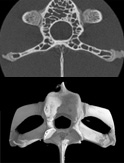

| 4. 高分辨率・高画质 | 超越5μm的空间分辨率 |

| 空间分辨率 | 5μm | |

| 分辨率 | 5μm | |||